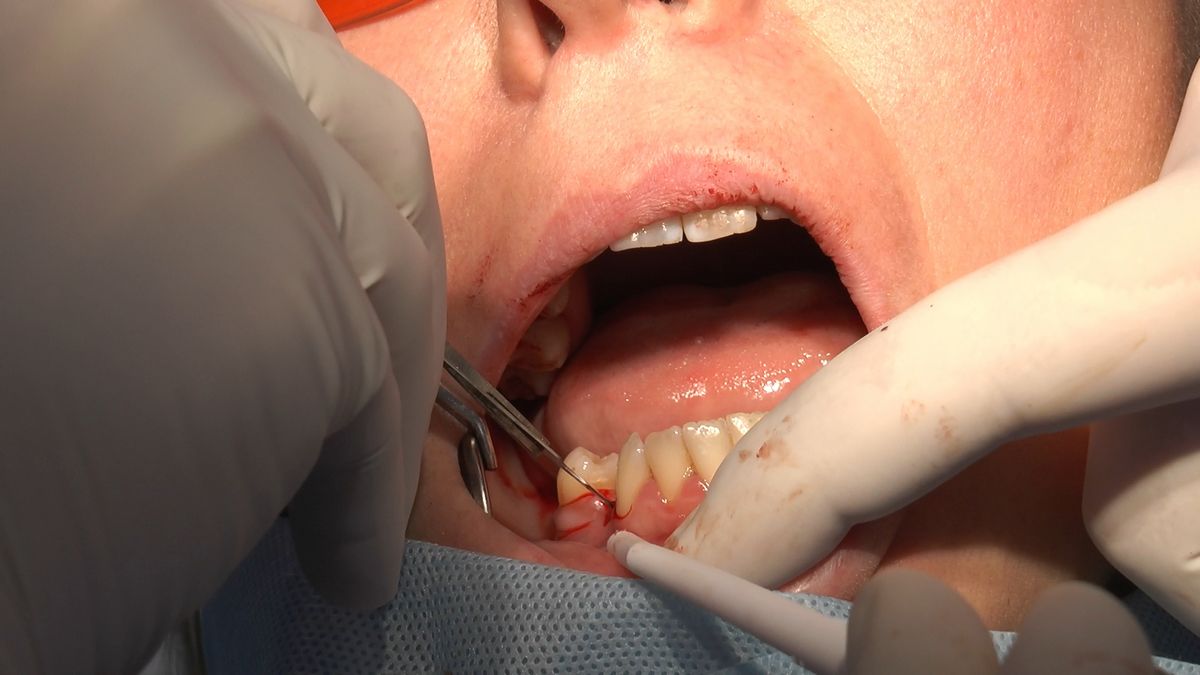

W ostatni weekend czerwca 2018 roku kursanci II Sezonu Preludium Implantologii odbyli piątą, finałową sesję, która w całości podporządkowana była praktyce. W ciągu dwóch dni zabiegowych Lekarze uczestniczący w szkoleniu przeprowadzili szereg zabiegów pod kierunkiem dr n.med. Violetty Szycik. Wszczepili 17 implantów oraz przeprowadzili ekstrakcje i zabiegi regeneracyjne kości. Zabiegi były wykonywane także w sedacji dożylnej z udziałem specjalisty anestezjologii i intensywnej terapii dr Jolanty Grzybowskiej. Preludium implantologii to nowy program edukacyjny dla adeptów implantologii stomatologicznej, którego celem jest wprowadzenie do implantologii poprzez pozyskanie wiedzy w szerokim zakresie i uwzględnieniem szczegółów mających decydujące znaczenie dla powodzenia leczenia implantologicznego. Ale tak jak wszystkie szkolenia w Instytucie Vivadental, w tym wiodące Practiculum Implantologii, zorientowane jest na praktyce i samodzielnym wykonywaniu zabiegów pod kierunkiem Mentora. To najlepsza edukacja w medycynie zabiegowej, a zarazem najlepszy start do implantologii.